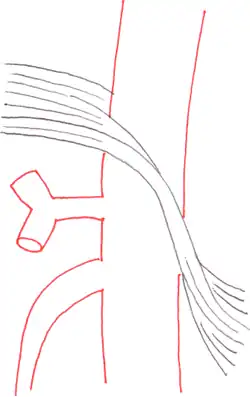

The median arcuate ligament is a ligament formed at the base of the diaphragm where the left and right diaphragmatic crura join near the 12th thoracic vertebra. This fibrous arch forms the anterior aspect of the aortic hiatus, through which the aorta, thoracic duct, and azygos vein pass. The median arcuate ligament usually comes into contact with the aorta above the branch point of the celiac artery. However, in up to one quarter of normal individuals, the median arcuate ligament passes in front of the celiac artery, compressing the celiac artery and nearby structures such as the celiac ganglia.[2] In some of these individuals, this compression is pathologic. It leads to the median arcuate ligament syndrome.[2]

Several theories attempt to explain the origin of pain caused by compression of the celiac artery.[5] One proposes that compression of the celiac artery causes ischemia, or decreased blood flow, to abdominal organs, leading to pain. Another hypothesis is that there is compression not only of the celiac artery but also of the celiac ganglia, and that pain results from compression of the latter.

Further evaluation and confirmation can be obtained via angiography to investigate the anatomy of the celiac artery.[5] Historically, conventional angiography was used, although this has been largely replaced by less invasive techniques such as computed tomography (CT) and magnetic resonance (MR) angiography.[2][5] Because it provides better visualization of intra-abdominal structures, CT angiography is preferred to MR angiography in this setting.[5] The findings of focal narrowing of the proximal celiac artery with poststenotic dilatation, indentation on the superior aspect of the celiac artery, and a hook-shaped contour of the celiac artery support a diagnosis of MALS.[2] These imaging features are exaggerated on expiration, even in normal asymptomatic individuals without the syndrome.[2]

Proximal celiac artery stenosis with poststenotic dilatation can be seen in other conditions affecting the celiac artery.[2] The hook-shaped contour of the celiac artery is characteristic of the anatomy in MALS and helps distinguish it from other causes of celiac artery stenosis such as atherosclerosis.[2] This hooked contour is not entirely specific for MALS however, given that 10–24% of normal asymptomatic individuals have this anatomy.[2]